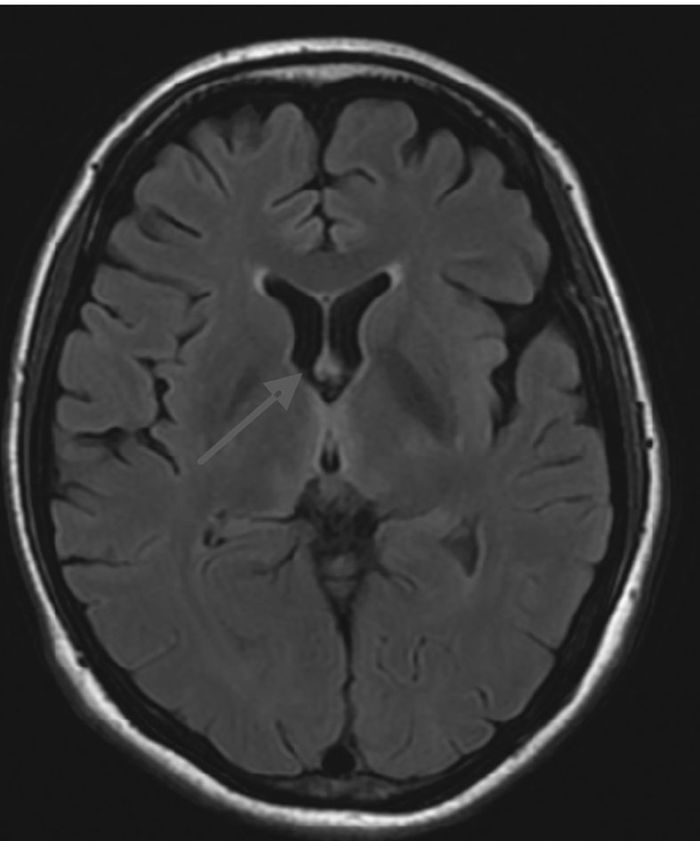

1 资料与方法患者女性,39岁,主因“复视1周,行走不稳4 d,意识障碍2 d”于2015年10月20日就诊北京大学人民医院急诊科。患者1周前出现复视,伴视物模糊、头晕,无头痛、恶心、呕吐。4 d前出现行走不稳,需家人搀扶,伴乏力。2 d前间断嗜睡,且意识障碍逐渐加重,后因呼之无反应,就诊当地医院行头颅CT示“脑桥可疑低密度灶”。既往:“慢性胰腺炎、慢性胆囊炎”3个月,进食差。否认药敏史。入院查体:T 37.8 ℃,HR 118次/min,RR 25次/min,BP 95/65 mmHg (1 mmHg=0.133 kPa),SpO2 90%。昏迷。双侧瞳孔等大等圆,直径3 mm,对光反射消失。双肺呼吸音粗,未闻及干湿性啰音。心率118次/min,律齐,心音较低,各瓣膜听诊区未闻及病理性杂音。腹软,肝脾肋下未触及。双下肢肌张力减低。病理征阴性。入我科后完善相关检查:血常规:WBC 6.28×109 L-1、Hb 104 g/L、PLT 279×109 L-1;生化全项:ALT 146 U/L、AST 81 U/L、ALB 40 g/L、GLU 6.87 mmol/L、TBIL 34.2 μmol/L、DBIL 15.3 μmol/L、Na+ 138 mmol/L、K+ 4.0 mmol/L、CRE 78 μmol/L;血气分析:pH 7.37,PaO2 168 mmHg (FiO2 29%),PaCO2 37 mmHg,SaO2 98%,Lac 2.7 mmol/L;头颅CT未见明显异常。初步诊断为意识障碍待查、肝功能损伤待查,予改善循环、营养神经、营养支持、护肝等治疗。考虑到患者院外饮食不佳近3个月,存在WE可能,予维生素B1 100 mg每日2次肌注。次日患者出现低氧血症,SpO2 78%~85%;血气分析:pH 7.36,PaO2 88 mmHg (FiO2 41%),PaCO2 30 mmHg,SaO2 83%,Lac 3.6 mmol/L;予气管插管接呼吸机辅助通气。10月28日脱机、拔除气管插管,予无创呼吸机序贯治疗。10月29日行头颅MRI示“双侧额叶皮层(图 1)、双侧丘脑、下丘脑、第三脑室、中脑导水管周围脑实质(图 2、图 3)异常信号影,符合Wernicke's脑病表现”,为进一步治疗收住院。入院后继续予营养神经、改善脑部血液循环、维生素B1 100 mg每日2次肌注等治疗。患者神志逐步恢复正常,可正常交流及缓慢行走,但表情淡漠、记忆力下降,复查肝功能正常,于2015年12月8日离院,门诊随访。

| 图 3 T2 FLAIR双侧丘脑、下丘脑、第三脑室、中脑导水管周围脑实质异常信号 |